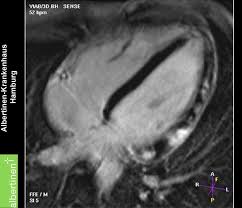

Dwi Mri Boosts Edema Detection In Acute Myocarditis

Dwi Mri Boosts Edema Detection In Acute Myocarditis from www.auntminnieeurope.com